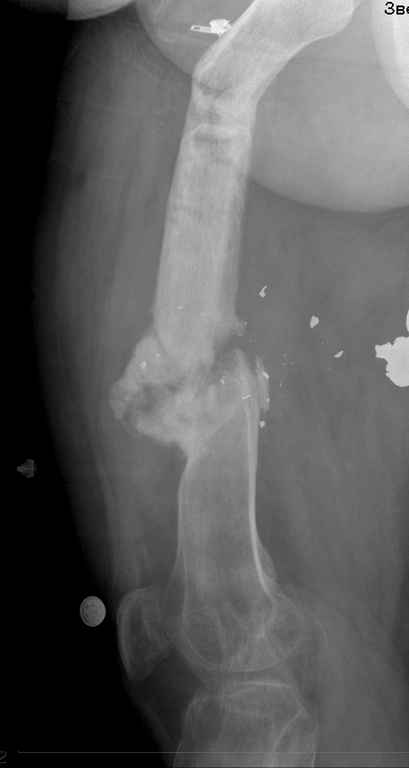

пациент имеет ложный сустав бедра после огнестрельного перелома и длительного лечения Пациент: 48л. ****** (ВРАЧ!) Инвалид 2 группы 3 степени Не работает Жалобы пациента: на невозможность полной нагрузки на левую нижнюю конечность, боли в левом бедре при движениях, в покое, патологическую подвижность в средней трети левого бедра, деформацию и укорочение конечности. Анамнез заболевания. : пациент получил открытый многооскольчатый огнестрельный перелом средней трети левой бедренной кости 24.12.2005г.. В экстренном порядке выполнялась хирургическая обработка раны левого бедра, наложение спице-стержневого аппарата внешней фиксации на левое бедро с вынужденным укорочением сегмента ввиду разрушения и отсутствия костных фрагментов. В послеоперационном периоде рана заживала вторичным натяжением удовлетворительно,без нагноения, выполнялась аутодермопластика дефекта кожи. Фиксация в спицестержневом аппарате в течение 5 месяцев. Правильной репозиции не удалось достигнуть. 24.5.06г. пациент в госпитале Самарского военно-медицинского института повторно прооперирован с установкой спице-стержневого аппарата на бедро и проведением остеотомии в в\3 бедра. Фиксация в аппарате в течение 19 месяцев. Ходил с дозированной нагрузкой на ногу. После снятия аппарата при увеличении нагрузки появилась варусная деформация бедра в зоне остеотомии, признаки образования тугого гипертрофического ложного сустава н\3 бедра. Анамнез жизни. Пациент аллергии на лекарственные препараты не отмечает. Туберкулез, вирусный гепатит, венерическую патологию отрицает. Гемотрансфузии были. Из перенесенных заболеваний отмечает калькулезный холецистит, оперирован в 2006 году – холецистэктомия, осложнившаяся перивезикулярным инфильтратом. Оперирован повторно. – ревизия, дренирование бр.полости. Аппендэктомия в 1993 году. прошу обсудить возможность восстановительного лечения, ПАЦИЕНТ НАСТОЙЧИВО ОТКАЗЫВАЕТСЯ ОТ АППАРАТЕ ВНЕШНЕЙ ФИКСАЦИИ, ИМЕЕТ БОЛЬШОЕ ЖЕЛАНИЕ ДОНОМОМЕНТНОГО ОСТЕОСИНТЕЗА С УСТРАНЕНИЕМ ДЕФОРМАЦИИ И УДЛИНЕНИЯ..

посылаю снимки отдельно

такое ощущение, что пациента на предыдущих этапах лечили только по снимкам нижней трети бедра в прямой проекции.